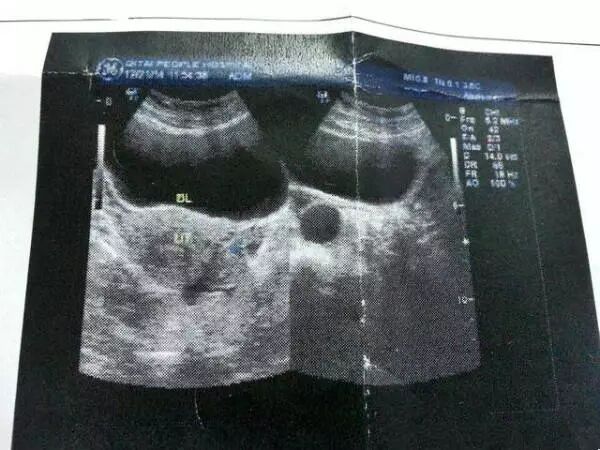

这几年发生生化妊娠的情况屡见不鲜,而很多孕妈去检查却发现也查不出个什么来。就像今年49岁的林女士,明明确诊为“怀孕”,可就在一星期后去复查,却被告知“未发现孕囊”,这让她十分心痛!

检查发现林女士体内并没有孕囊

HCG也下降到正常数值

这些报告单都显示她并没有怀孕

是指精卵结合了,一般精卵结合七天以后就要分泌绒毛膜促性腺激素,再过七天以后,用早孕试纸就可以测出来,往往精卵结合了,有分泌了,但是必须结合成受精卵,受精卵还要回到子宫里着床,生化妊娠就是结合了,但是没有回到子宫里着床,或者是回来了,没有着上床,这种就叫生化妊娠。